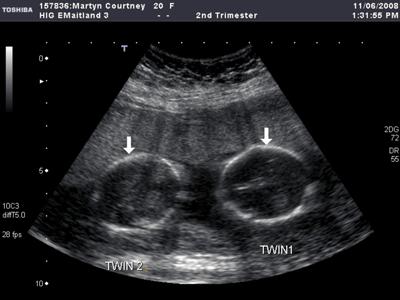

Всего лишь пару десятилетий назад, будущая мать могла узнать о появлении на свет сразу двух деток только в момент родов. Сегодня, когда настал век, стремительно развивающихся новых технологий, с помощью ультразвукового исследования, об этом узнают уже на начальных сроках беременности. Примерно начиная с десятой недели беременности, врач может определить с помощью аппарата УЗИ наличие двух плодов, которые развиваются одновременно.

Врач, в свою очередь, примерно на тринадцатой неделе начинает прослушивать двойное сердцебиение, что так же свидетельствует о наличии двойни.